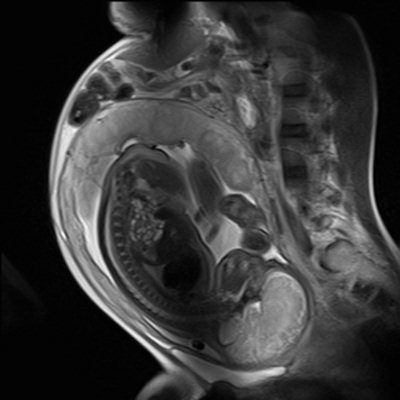

Kısaca MR (emar) olarak bilinen ‘manyetik rezonans’ işlemi 30 yıldan fazla zamandır hamile kadınlardaki obstetrik, plasenta ve ceninle ilgili anormallikleri tespit etmek için kullanılan bir görüntüleme yöntemidir. Bir görüntüleme yöntemi olarak faydalı bir teşhis aracı kabul edilen MR, anne adayı ile fetüsü etkileyen çok çeşitli hastalıkları tespit edebilir.

MR ile ilgili merak edilen diğer bir nokta ise, ilk trimester denilen hamileliğin ilk 3 ayında çekim yapılıp yapılamayacağı… Bu konuda yapılan bilimsel çalışmalarda yine herhangi bir yan etki görülmemiştir. Ancak hekimler tedbir olarak ilk üç ayda acil bir durum yoksa, MR çekiminin bir sonraki trimestere bırakılmasını tercih ediyor. Acil ve gerekli durumlar olduğunda ise bu süreyi beklemeye gerek duymuyorlar. Anne karnındaki bebeğin sağlıklı olup olmadığını anlamak için, zaman kaybetmeden ‘fetal MR’ görüntüleme yapılması gerekebiliyor. Bebeğin sağlığını ilgilendiren hastalıklarda ultrasonografinin tanı için yetersiz kaldığı durumda ya da tanıyı desteklemek için yapılan Fetal MR ile fetüsün başta beyin, omurilik ve karın içi organları olmak üzere diğer tüm organları ile ekstremiteleri (bacak-ayak-el ve kol) değerlendiriliyor. Hamileliğin 24. haftasından itibaren uygulanabilen fetal MR, fetüsün ve plasentanın değerlendirilmesi açısından ultrasonografiden daha güvenilir sonuçlar veriyor”